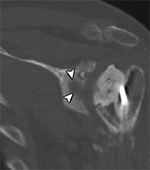

Hardware Infection. Coronal multiplanar reformation of the shoulder demonstrates post-surgical changes following removal of infected left total shoulder arthroplasty with placement of antibiotic spacer and glenoid osteolysis (arrowhead) due to ongoing infection.